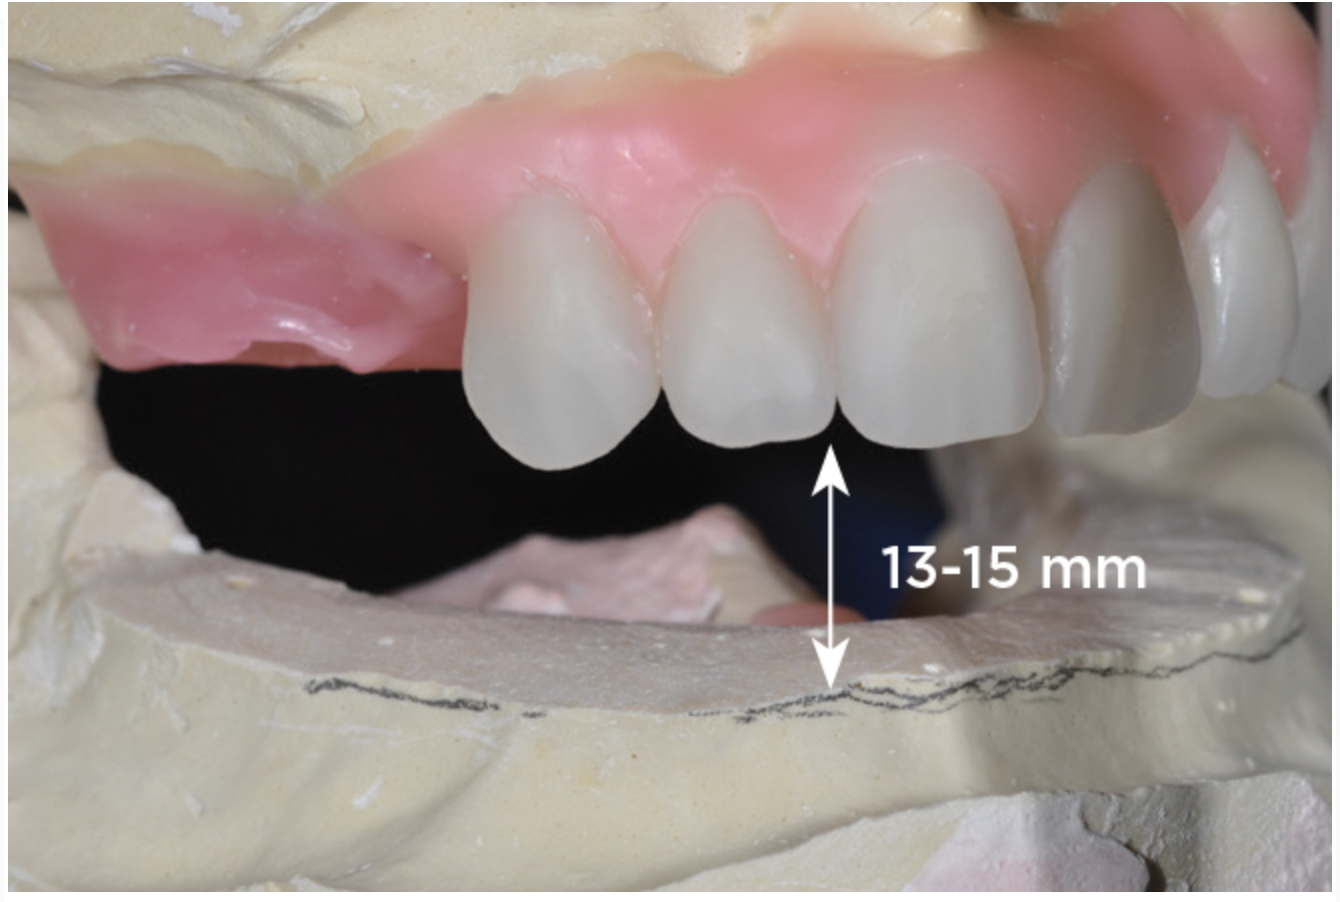

An important advantage of this approach is the ability to simulate bone reduction on the models and verify the presence of 15 mm to 17 mm and 13 mm to 15 mm of required inter-occlusal space for maxillary and mandibular restorations, respectively. This creates a platform for a diagnostic wax-up of the proposed dental rehabilitation and fabrication of wax prosthesis try-ins when necessary. Finally, a modified All-on-4 provisional prosthesis surgical and restorative guide developed by the authors for restoration-driven surgery and simplified restorative procedures is fabricated (Figure 2 through Figure 8).

Fig 5. Bone reduction model surgery performed in mandibular arch to create 13 mm to 15 mm of inter-occlusal space required for the mandibular All-on-4 provisional restoration.

Figure 5